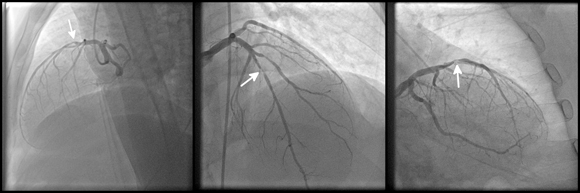

כל סימן נוסף בתמונה מלבד הדגימה או הצילום הרפואי עצמו – עלול לגרור אימון שגוי של האלגוריתם. תמונת דימות של מחלת לב כלילית | kalewa, Shutterstock